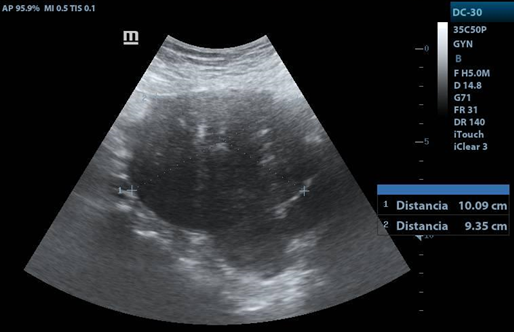

Transvaginal USG: uterus in AVF 4.5x5x3.3cm, LE 12.3mm. Right ovary: 4.8x3.6x3.7 cm vol. 34cc, with a tumor measuring 11.2x8.6cm, solid, with homogeneous and hypoechoic echotexture, with posterior acoustic shadow and Doppler flow uptake. Left ovary: 5x5x2.2cm vol. 19.6cc.

3. The characteristics of fibrothecomas by ultrasound are adnexal hypoechoic masses with a clear border and acoustic attenuation, as well as minimal Doppler flow signals. They are usually unilateral.

USG Transvaginal

1. Right adnexa, with heterogeneous image, hypoechoic mass, with clear border. with distance of 11.26X11X8.6cms.

1. Acoustic attenuation posterior a hypecoic mass en right adnexa.